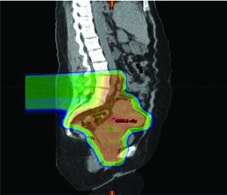

A terapia com prótons pode ser considerada como alternativa de boost para pacientes que não podem receber braquiterapia. Prótons apresentam vantagens dosimétricas em bexiga, intestino, cabeças femorais e reto em comparação ao VMAT. O CTV de boost pode ser determinado por RM obtida após 3 semanas de quimiorradiação, administrando-se então 30 Gy/Gy equivalente em 5 frações em substituição à braquiterapia. Entretanto, evidência prospectiva de alta qualidade ainda é insuficiente, e a relação entre dosimetria melhorada e redução clinicamente significativa de toxicidade permanece sem comprovação definitiva.

SBRT para Câncer Cervical

No câncer cervical locorregionalmente avançado, o padrão de tratamento combina EBRT fracionada diária com cisplatina concomitante seguida de boost com braquiterapia, alcançando dose EQD2 final de 80 a 95 Gy no alvo. A SBRT surge como modalidade especializada que entrega doses altas em 1 a 5 frações, exigindo visualização precisa do alvo, delineação acurada de tumor e OARs, e posicionamento de alta fidelidade com guia de imagem.

A SBRT permite entrega conformal de boost em alta dose, mas resultados recentes exigem cautela. Um ensaio fase II investigando SBRT (28 Gy em 4 frações) como substituto da braquiterapia foi encerrado prematuramente por toxicidade maior que a esperada e taxas de controle local, sobrevida livre de progressão e sobrevida global inferiores ao previsto em 2 anos. Braquiterapia permanece o padrão de tratamento para pacientes elegíveis.

Para pacientes que definitivamente não receberão braquiterapia, um esquema de 5 frações (por exemplo, 27,5 Gy em 5 frações) após 45 Gy na pelve pode ser considerado, resultando em EQD2 de 80 Gy (α/β = 10). A determinação de dose e fracionamento deve considerar o tamanho do alvo, RT prévia na área e tolerância dos OARs adjacentes. Para regime de 5 frações, a dose por fração situa-se tipicamente na faixa de 4 a 8 Gy, embora frações de 8 a 15 Gy também tenham sido reportadas. A EQD2 total deve ser calculada para a área tratada. Para entender melhor a SBRT em outros cenários, confira nosso artigo dedicado sobre SBRT em cabeça e pescoço.